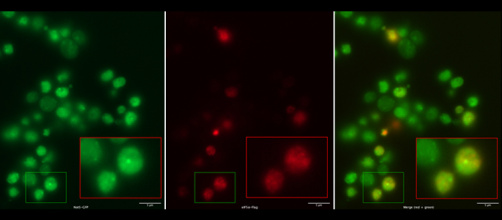

Des immunothérapies efficaces contre les cancers colorectaux

Comment la sérotonine freine l’addiction à la cocaïne